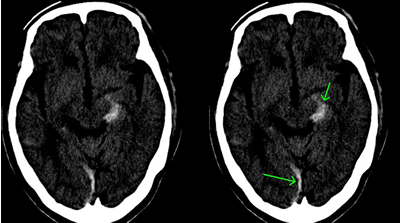

左顔面部を強打した脳挫傷の事例

CT画像では、中央部右側に白い○状の形があるのが読み取れます。これが脳挫傷が生じた部分です。

これは、バイクを運転していたところ、自動車と出合い頭で衝突した被害者のものです。左顔面部を強打し、左下顎骨骨折、左頬骨骨折となり、左下からの突き上げる衝撃で、左側頭葉に局在性の脳挫傷が発症したものです。

左側頭部を強打した脳挫傷の事例

CTの3D画像では骨折線が確認できます。CT画像では矢印のところに異常があります。

自転車に乗っていたところ、軽自動車と出合い頭で衝突した被害者のものです。左側頭部を骨折し、その衝撃により、打撲部位の直下の脳組織が挫滅となりました。これも、局在性の脳挫傷です。

対側損傷の具体例

CTは前頭葉左側部の頭蓋骨骨折と脳挫傷の合併症です。対側損傷が発生し、対角線上の右後頭部に脳挫傷を発症しています。